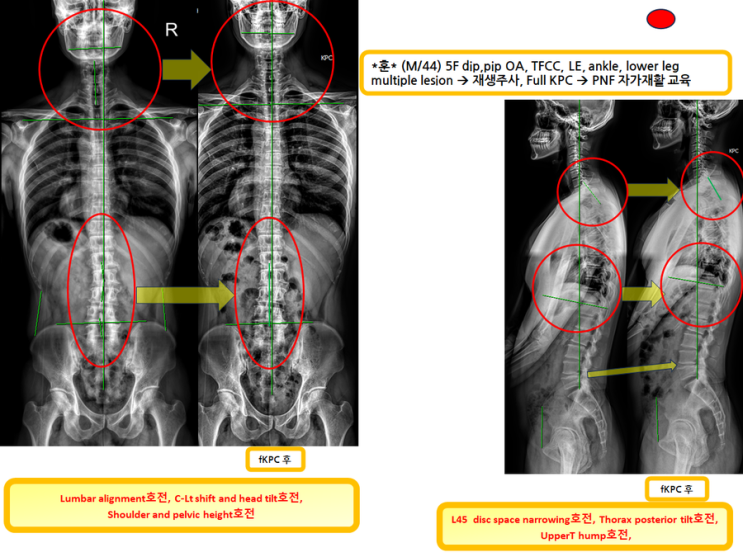

3번째 full KPC하신 분!(엑스레이 호전을 10분만에 확인하는 녹는실KPC)

3번째 full KPC하신 분! (엑스레이 호전을 10분만에 확인하는 녹는실KPC) 바늘을 무서워하여 1달반, ...